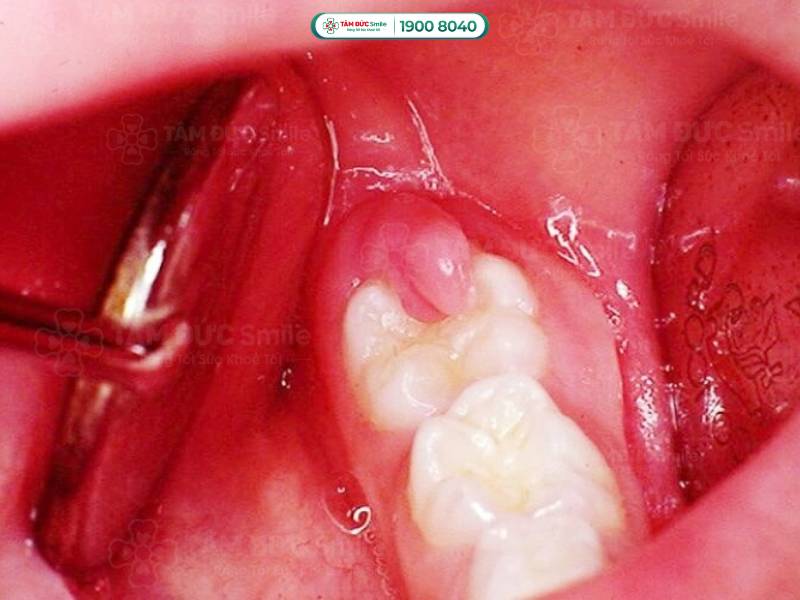

Bị áp xe răng ở vị trí răng số 7

- Khi bọc mủ bị vỡ sẽ tạo ra các "lỗ rò" để giải phóng mủ bên trong. Lúc này, bạn thấy được phần nướu sưng tấy đặc trưng của tình trạng nhiễm trùng.

- Mô nướu sưng và chứa đầy mủ. Phần lợi bị sưng to, nhìn như mọc cái mụn ngay cạnh răng hàm.